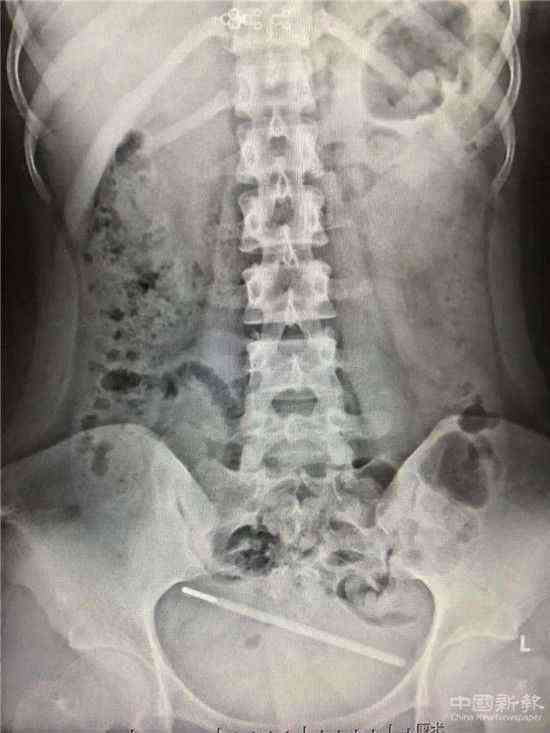

中國新報貴州訊(楊曉涓 記者 羅茜 劉鵬飛 攝影報道)近日,貴州凱里一女子測量體溫時,不慎將體溫計塞入尿道致其進入了膀胱,險些釀成了嚴重后果,事發(fā)后,黔東南州人民醫(yī)院的醫(yī)生為她進行了一場驚心動魄的手術(shù),最終化險為夷。

(溫度計在體內(nèi)的狀況)

醫(yī)護人員經(jīng)過詢問得知,女孩由于發(fā)燒自己在家測量肛溫,卻不慎將體溫計塞入尿道并由此進入膀胱,短短幾小時后就出現(xiàn)劇烈腹痛、腹脹、尿頻、尿急、血尿等癥狀。

鑒于此,楊主任立即安排患者進行膀胱鏡檢查,檢查過程中發(fā)現(xiàn)體溫計部分已進入到腹腔。

楊主任拿出的救援方案是,通過膀胱鏡將異物從腹部取出,但是幾經(jīng)嘗試,因玻璃體溫計材質(zhì)太滑,用輸尿管鉗子和膀胱鏡鉗根本夾不住,就像空手抓泥鰍一樣,越夾越往里滑,體溫計不僅沒取出,還進一步往腹腔滑動,留在膀胱僅2cm不到,如果再次嘗試就可能將體溫計完全推進腹腔,一旦體溫計破損造成水銀外泄,那后果將不堪設(shè)想……